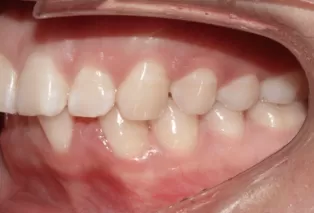

Female, 25 years old. Chief complaint: protruding and misaligned teeth, requiring orthodontic treatment.

Intraoral photos